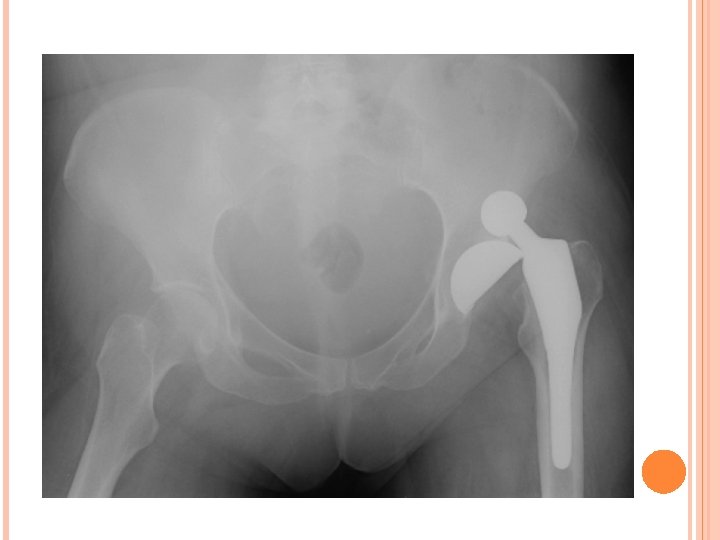

FEM FX CON’T Treatment – � Immobilized and transported for immediate medical care. Physician will either do a close reduction, or open reduction, depending on placement of fracture and number of fracture sites. ORIF (open Reduction Internal Fixation) requires pins and rods � Following surgery, ath will be immobilized in hinge brace and will require PT. Rehabilitation typically takes 4 months